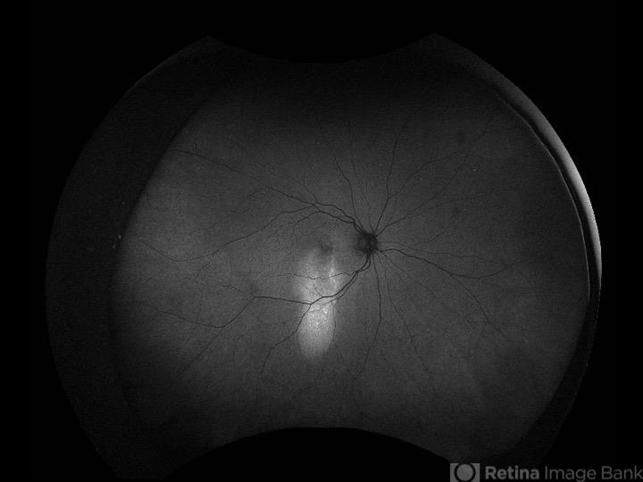

- ultra-wide field imaging, OPTOS CALIFORNIA, chronic central serous chorioretinopathy (CSCR), autofluorescence imaging

- Ultra-wide field autofluorescence of an 61-year-old woman with chronic central serous chorioretinopathy with a gravitational tract